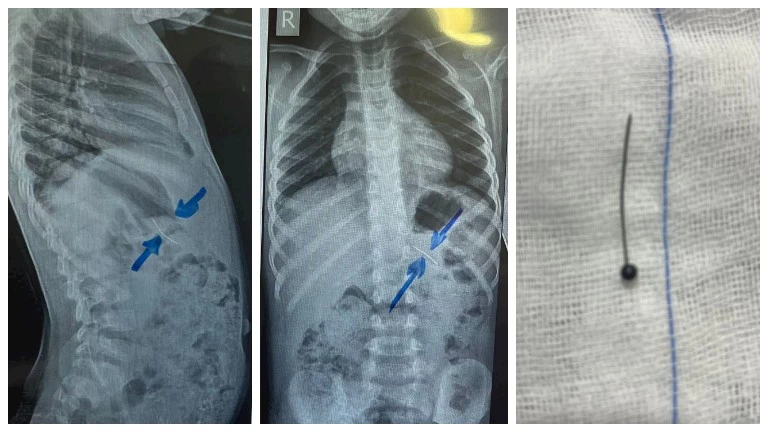

نجح فريق طبي من وحدة أمراض الجهاز الهضمي والكبد ومناظير الأطفال بقسم طب الأطفال بمستشفى سوهاج الجامعي، في إجراء تدخل دقيق لاستخراج دبوس من معدة طفل يبلغ من العمر أربع سنوات، بإستخدام منظار معدة خاص بالأطفال، دون حدوث أي مضاعفات، وغادر الطفل المستشفى بعد ثلاث ساعات فقط من الإجراء، وهو في حالة صحية جيدة.

وأكد الدكتور أحمد كمال، المدير التنفيذي للمستشفيات الجامعية، أن التعامل مع الحالة تم بسرعة وكفاءة، حيث تمكن الفريق الطبي من استخدام المنظار الخاص بالأطفال لاستخراج الدبوس دون أي تدخل جراحي، مما ساهم في خروج الطفل من المستشفى في نفس اليوم بحالة ممتازة.